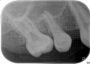

当時の歯の移植は、移植歯を抜歯したら、歯の根の表面の徹底的な清掃(掻爬)と、根管治療を口腔外で行いその歯を移植していました。しかし、それでは移植歯は移植された所の歯槽骨(もともとの歯を支える骨)とどんなに上手くいっても骨性癒着を起こします。この癒着した歯の根は時間と共に周囲の骨組織に吸収され、やがて歯の根はあとかたも無くレントゲンから消え去り、まるで乳歯が抜けるように根の無くなった歯が抜けていきます。これが5年もてば成功といわれた所以です。

現在は、ドナーとなる歯の抜歯前に移植される側の処置を終了し、ドナーの歯を抜歯するとほぼ同時に、当院では3秒以内に受容側の中にドナーの歯を入れます。これはとても速いスピードであるといえ、このスピードで確実に行う為に、いろいろな研究を行い、CTスキャンのデータを応用した現在の移植のシステムを構築致しました。

このようにして移植された歯は、歯の根の表面にある歯根膜と言う組織がほぼ完全に保存され、生着(生きた状態で移植されて機能する事)する事によって、将来矯正治療で歯を移動する事もできますし、被せもの等を行えば全く移植歯である事は気が付かれないレベルで仕上がります。